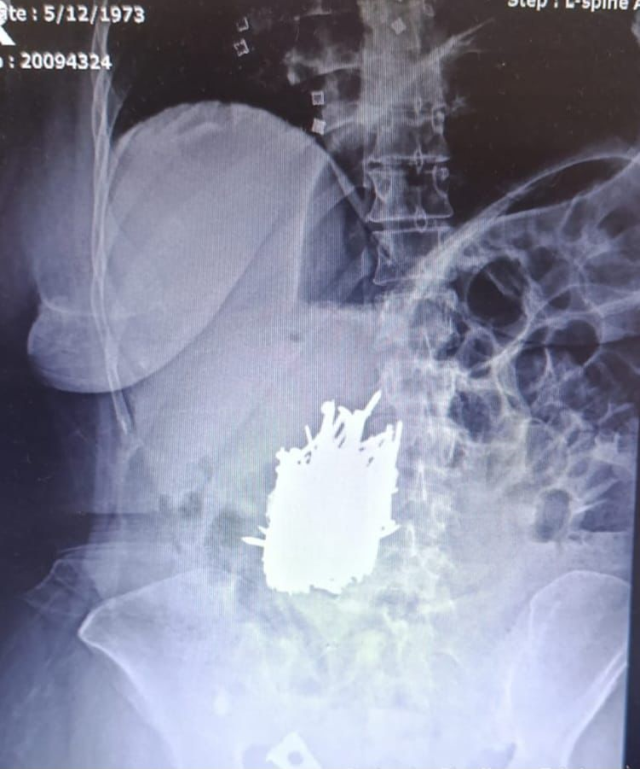

Mersin'in Erdemli ilçesinde yaşayan zihinsel engelli bir kadın, karın ağrısı şikayetiyle hastaneye başvurdu. Acilen ameliyata alınan kadının midesinden yaklaşık 1 kilo ağırlığında çivi, inşaat demiri, kolye, toka gibi çok sayıda metal cisim çıkarıldı.

Mersin'in Erdemli ilçesinde zihinsel engelli kadın hastanın midesinden 1 kilo metal cisim çıktı. İlçede yaşayan zihinsel engelli A.K., karın ağrısı şikayetiyle Erdemli Devlet Hastanesi'ne başvurdu. Hastaya yapılan tetkik sonucunda kadının midesinde çok sayıda metal cisim olduğu tespit edildi.

Hasta, genel cerrahi uzmanı Dr. Can Terzier ve ekibi tarafından acilen ameliyata alındı ve midesinden yaklaşık 1 kilo ağırlığında çivi, inşaat demiri, kolye, toka gibi çok sayıda metal cisim çıkarıldı.